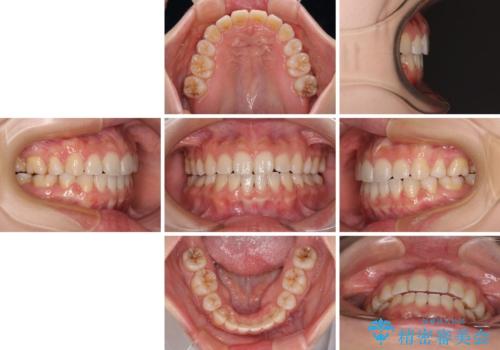

- 前歯が突出しているために口が閉じられないとのことで来院された患者様です。

上下ともに顎が小さく、歯列が前方に突き出していたため、上下左右の第一小臼歯4本を抜歯し、口元の突出感を改善していくこととしました。

口元の突出感が改善されると睡眠中の口呼吸が予防でき、鼻炎などの疾患予防に繋がると言われています。